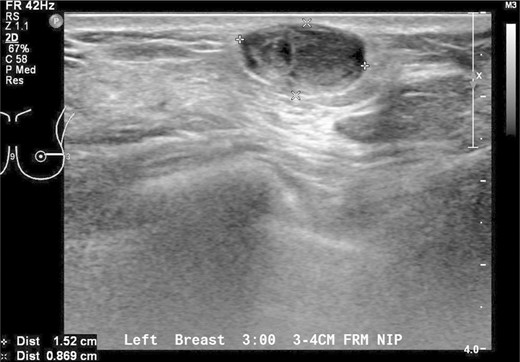

A 37-year-old Chinese female presented with a lump in the left breast that was slowly growing over a duration of 8 years. Aside from a history of amenoblastoma of the jaw which was excised 3 years ago, she has no significant medical history. On physical examination a firm 1-cm nodule was palpable at the 3 o'clock position of the left breast. Mammography showed a well-circumscribed opacity in the left breast (Fig. 1) and ultrasound revealed an ovoid 1.5 × 1.5 × 0.9 cm heterogeneous solid hypoechoic nodule with well-defined, regular margins (Fig. 2). The lesion contained some anechoic areas suggestive of cystic clefts which are consistent with sonographic features of a phyllodes tumour [1, 2].

Sonographic views of an ovoid well-marginated nodule containing some cystic clefts. This lesion was initially thought to represent a phyllodes tumour.